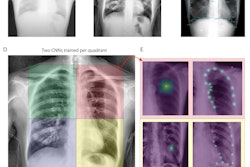

A graphical abstract. Hemodynamic assessment is essential for heart failure monitoring and assessment; however, it is invasive and is associated with complications. Dynamic chest x-ray (DCR) is a novel, minimally invasive, low-cost, and versatile imaging modality that can be used to visualize cardiac and pulmonary blood flow as pixel values, which correlate with hemodynamic parameters. Thus, DCR may be a useful alternative to estimate hemodynamic parameters in patients with HF. Image and caption courtesy of the European Journal of Radiology through CC BY 4.0.First, the researchers calculated right atrial, right pulmonary artery, and left ventricular apex pixel values in the dynamic chest radiography images. Next, they analyzed correlations between rates of change in these pixel values with right atrial pressure, pulmonary artery pressure, pulmonary artery wedge pressure, and cardiac index findings from the catheterization procedures.